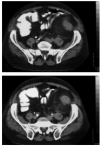

Se trata de un paciente fumador y bebedor, diagnosticado de colon irritable con dos brotes anuales tratados con septrim. Acude a urgencias de un hospital comarcal por cuadro diarreico y febrícula de 3-4 semanas de evolución que se autotrata con Septrim. En las últimas 24 horas presentaba fiebre de 38° C y dolor en fosa ilíaca izquierda. Queda ingresado en dicho centro presentando a las 24 horas inestabilidad hemodinámica, leucopenia y plaquetopenia severas. Se realiza tomografía axial computarizada (TAC) abdominal (figs. 1 y 2) en la que se aprecia un engrosamiento de sigma y colon izquierdo con cambios inflamatorios compatibles con diverticulitis aguda, presenta además aire en vena mesentérica inferior y en todo el eje esplenoportal, sugestivo de pileflebitis. Se inicia tratamiento con inotrópicos (dopamina, dobutamina y noradrenalina) y antibióticos (gentamicina, imipenem y metronidazol) y es remitido a nuestra unidad.

Figura 1. Presencia de gas en sistema venoso portal y vena mesentérica inferior.

Figura 2. Engrosamiento de sigma con cambios inflamatorios compatibles con diverticulitis.